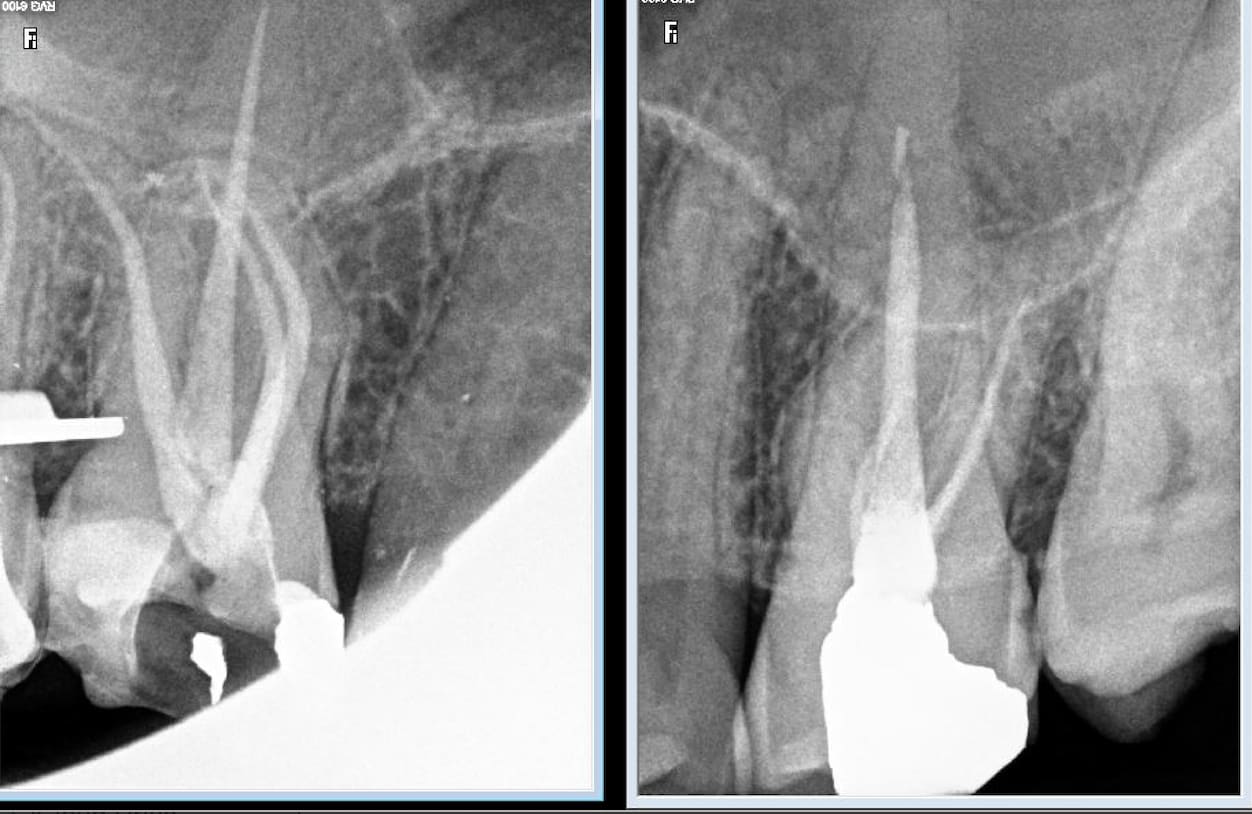

Comparaison des traitements de 2 praticiens différents au même tarif. Même patient 16 26. Pourquoi se faire chier aucun souci sur 26. ,

> Comparaison des traitements de 2 praticiens différents au même tarif. Même

> patient 16 26. Pourquoi se faire chier aucun souci sur 26. ,

c est terrible parce que selon Gabzou... le gars qui a foiré l endo 26 a fait exprès puisque c est facile...

Indépendamment du reste, il y a clairement une racine MV non traitée dont on distingue le canal, ce qui est l'anatomie standard d'une 26.

Conclusion, le praticien l'a sciemment ignorée pour aller plus vite.

On peut discuter de la rémunération, des raisons qui ont amené ce praticien à choisir de bâcler le travail, mais il est indiscutable que le praticien ne peut pas avoir ignoré avoir fait n'importe quoi.

J'ai bien précisé que tout n'est pas facile. Cette 26 l'est, je n'ai quasiment aucun doute.